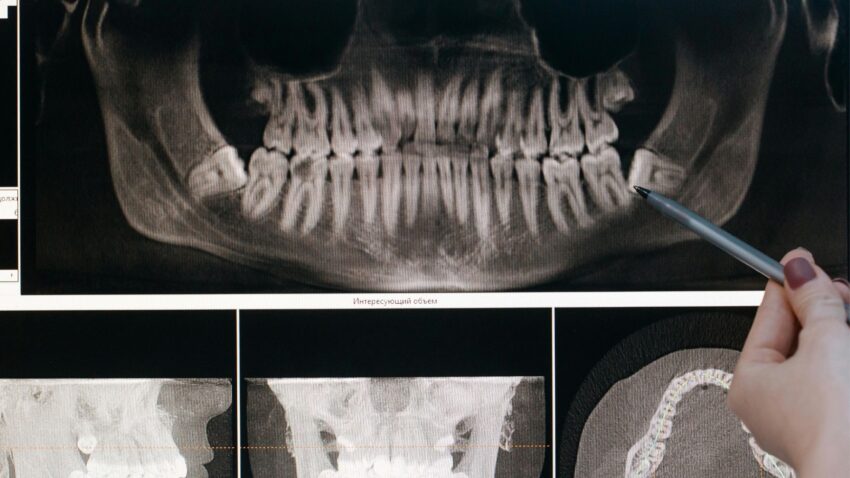

A bölcsességfogak eltávolítása mellett szóló érvek között szerepel, hogy nehezen tisztíthatók, ezért könnyen szuvasodnak, valamint gyakran nekidőlnek a szomszédos fogaknak, károsítva azokat. Rágásban már nincs jelentős szerepük, viszont gondozásuk, esetleges kezelésük különösen nehézkes lehet elhelyezkedésük miatt. A panoráma röntgenfelvétel elkészítése elengedhetetlen lépés a bölcsességfog állapotának felméréséhez és a megfelelő kezelési terv kialakításához. A korai diagnosztika és beavatkozás segíthet elkerülni a későbbi, esetleg súlyosabb komplikációkat.

A bölcsességfog műtét folyamata a MyDent rendelőben minden esetben alapos előkészületekkel kezdődik, amelyek során panoráma röntgenfelvétel és szükség esetén CBCT (fogászati CT) készül. Ezek alapján a fogorvos pontosan meg tudja határozni a bölcsességfog helyzetét és a műtét optimális módját, különösen akkor, ha a fog részben vagy teljesen a csontban fekszik. A beavatkozás során első lépésként feltárják a bölcsességfogat, majd szükség esetén szeletekre vágják és így távolítják el, végül gondosan kitisztítják a sebet és összevarrják.